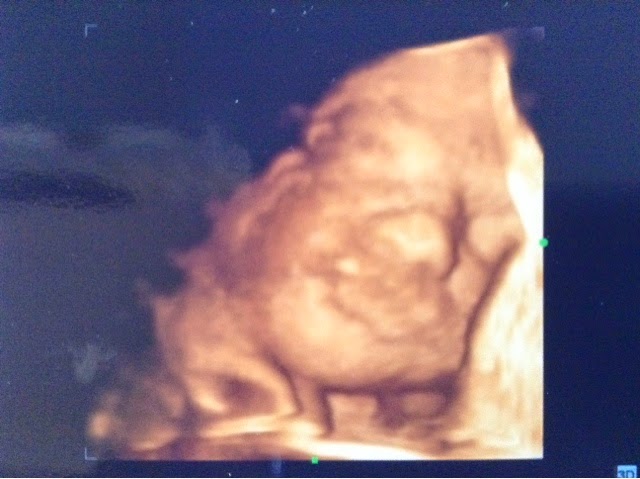

4D scan